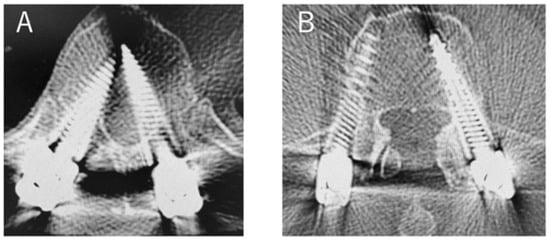

Figure 2.

PPS insertion in lateral decubitus position ((A); Thoracic spine. (B); Lumbar spine).